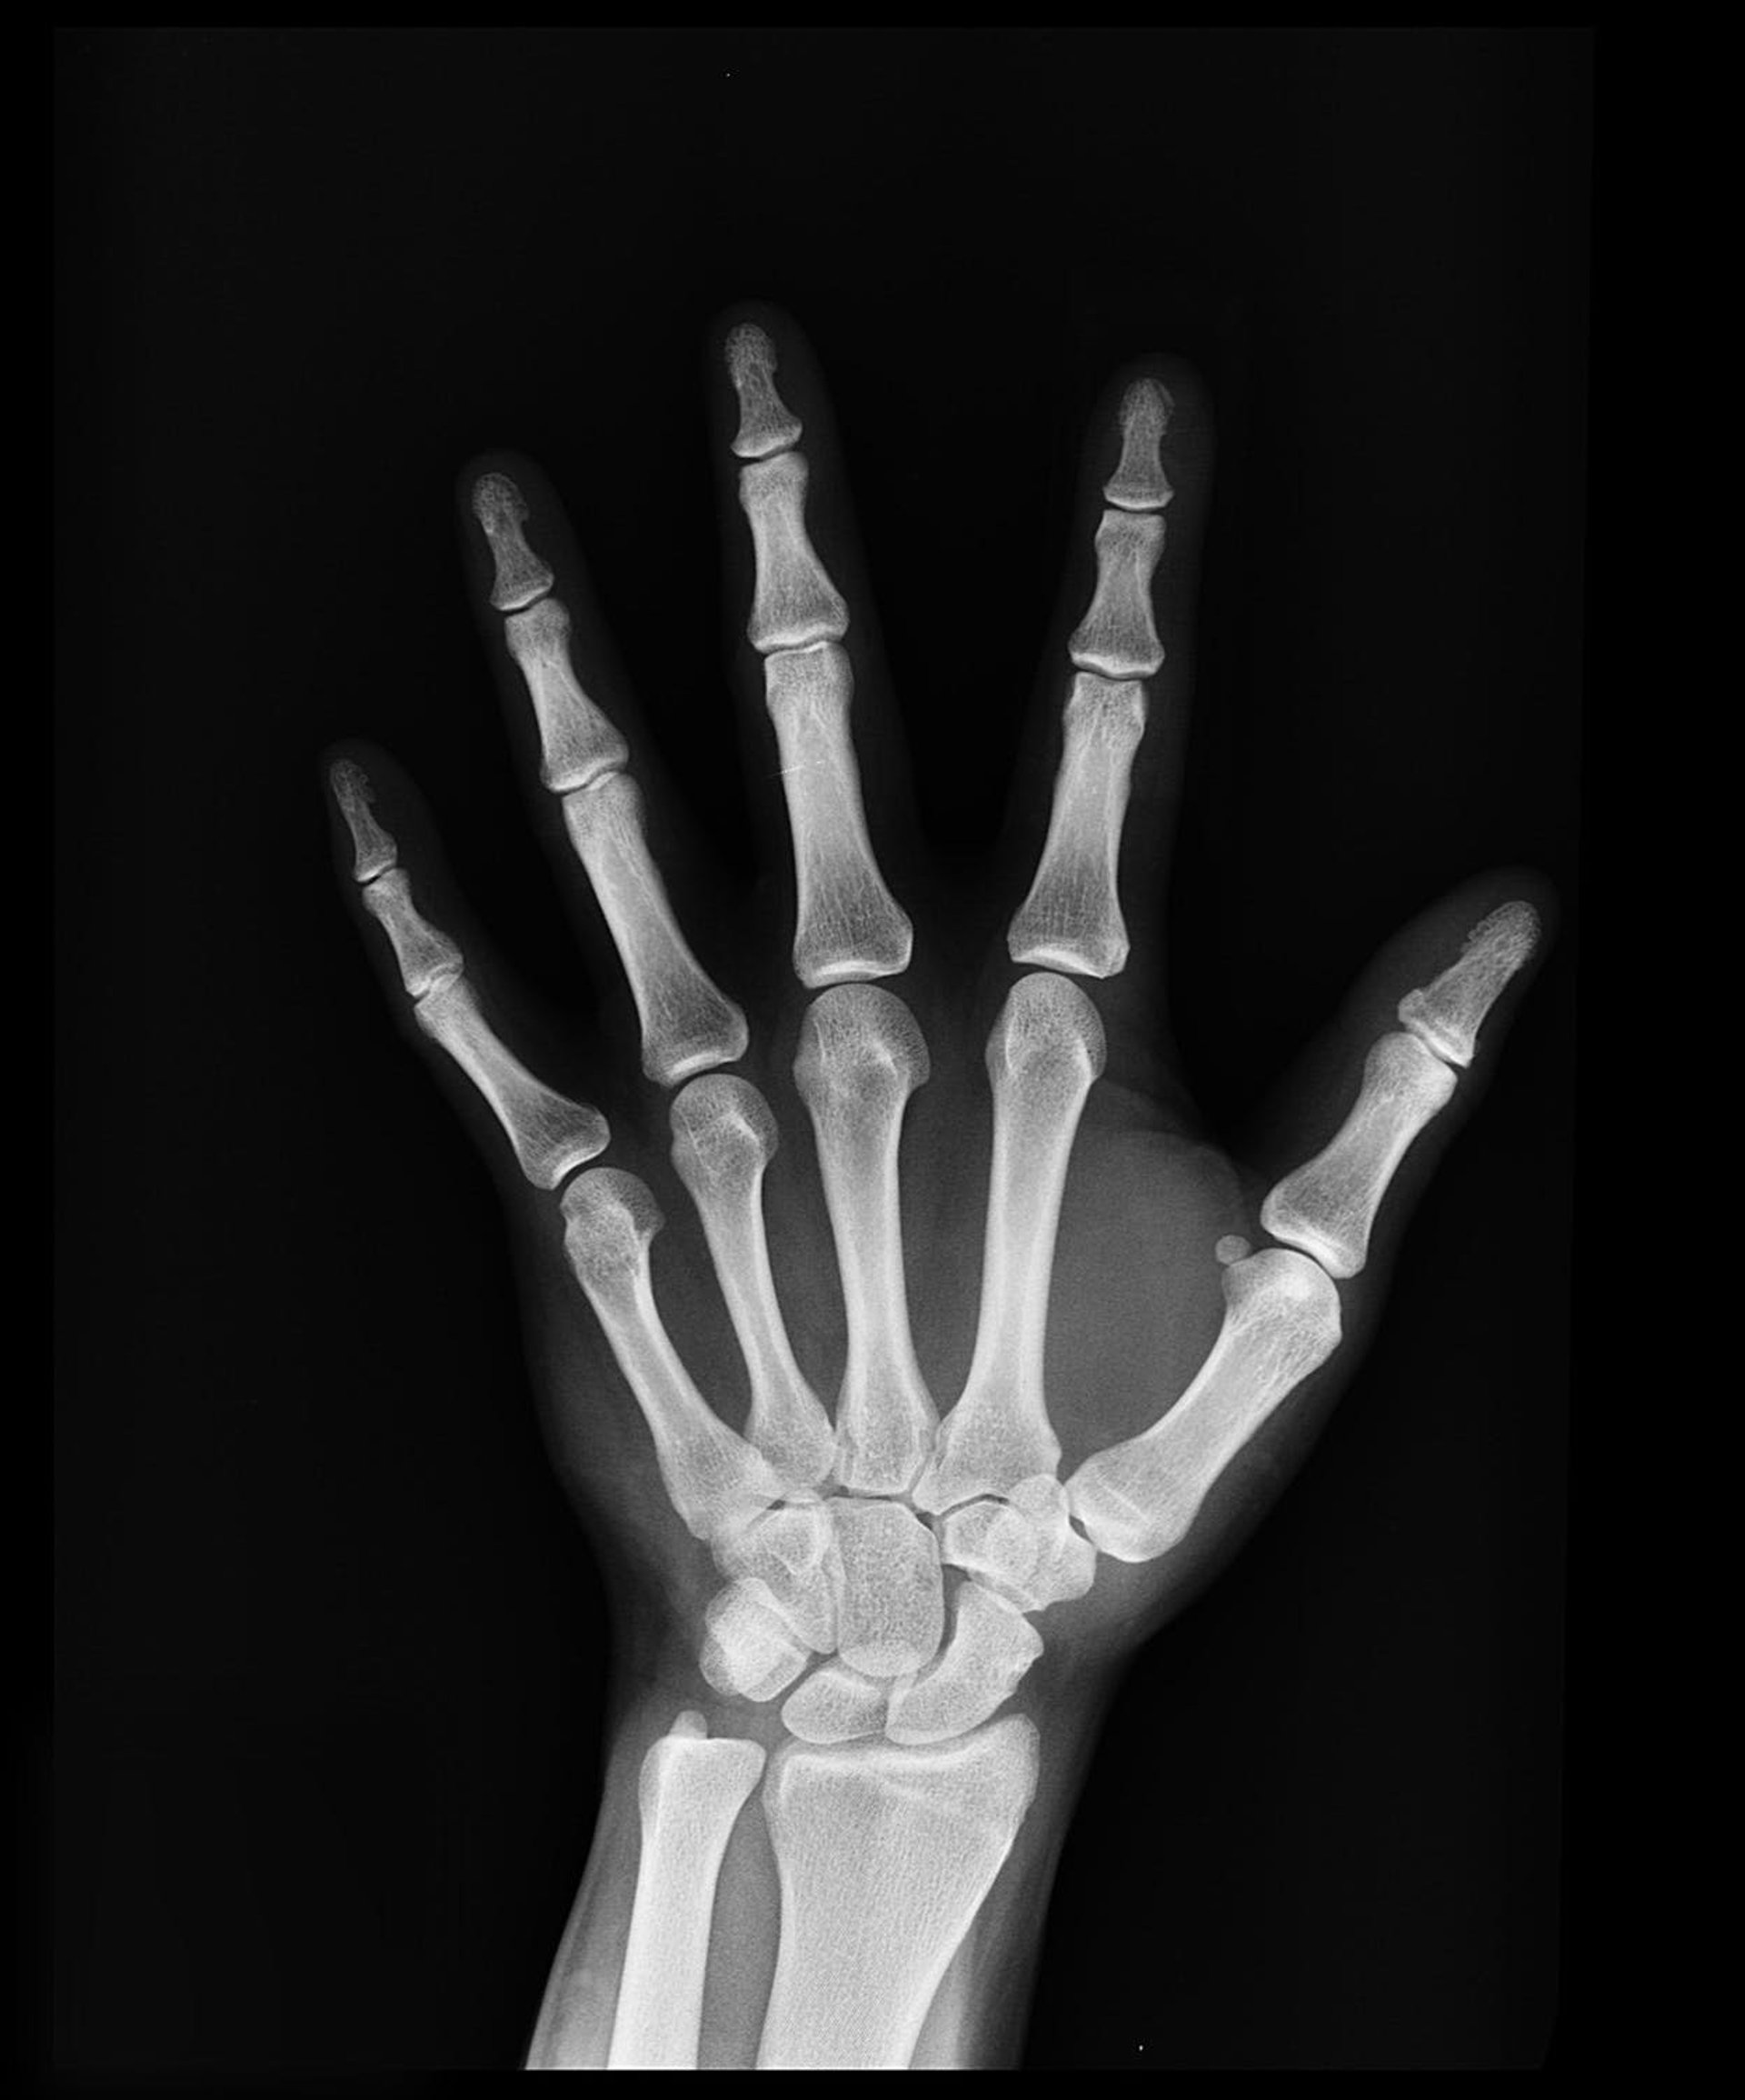

Radiografía de mano

Radiografía de mano - UGR